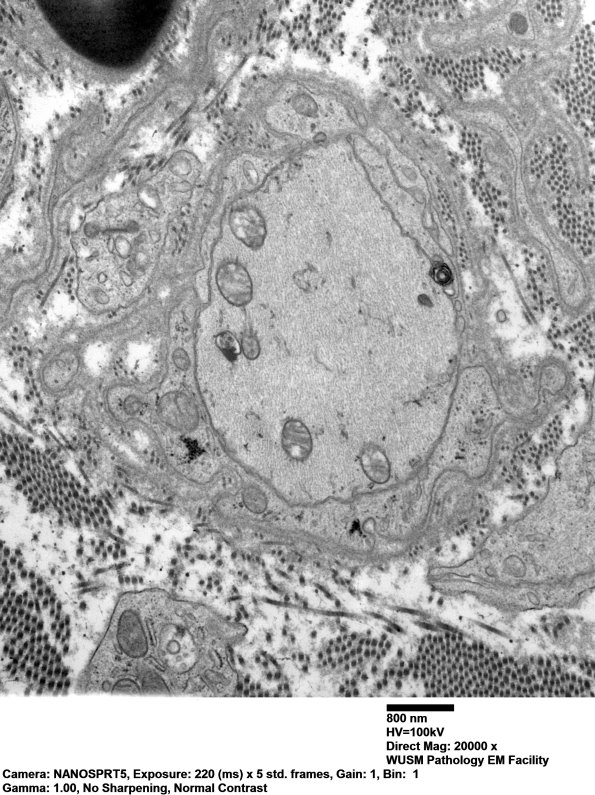

The number of demyelinated axons is significantly greater than anticipated from the one micron plastic sections. (electron micrographs)